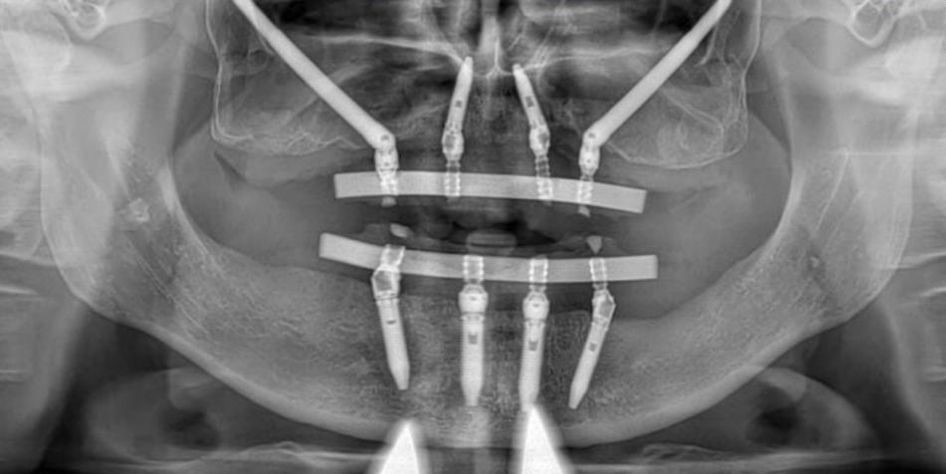

Nel caso che vi proponiamo, il paziente non aveva più denti nell’arcata superiore e presentava una grave carenza di osso mascellare. Nell'arcata inferiore, invece, aveva pochi denti residui, non più recuperabili e non idonei al nuovo progetto protesico. Il Dott. Cesare Paoleschi ha operato il paziente presso la sala operatoria del centro chirurgico Iris di Viareggio, supportato dal suo intero team di chirurgia. L’intervento, eseguito in anestesia generale, ha previsto:

l’inserimento di due impianti zigomatici e due impianti endossei nell’arcata superiore;

l’inserimento di 4 impianti endossei nell’arcata inferiore (tecnica Allon4).

Gli impianti dentali zigomatici sono impianti di dimensioni più lunghe rispetto a quelli tradizionali che si vanno ad innestare direttamente nello zigomo, un osso molto resistente e idoneo all'integrazione dell'impianto. Grazie a questa tecnica è così possibile creare un assetto implantare solido in modo da garantire la stabilità della protesi dentaria.

Al termine dell’intervento chirurgico, mediante un apposito dispositivo (chiave dinamometrica), il Dott. Cesare ha valutato la buona stabilità degli impianti e predisposto il carico immediato. Grazie a questa tecnica è possibile avvitare la protesi fissa agli impianti a distanza di poche ore dall’intervento chirurgico, evitando al paziente il disagio di restare senza denti. Dopo pochi giorni, infatti, il paziente ha effettuato una visita di controllo durante la quale gli sono stati già avvitati agli impianti le due nuove protesi dentarie.